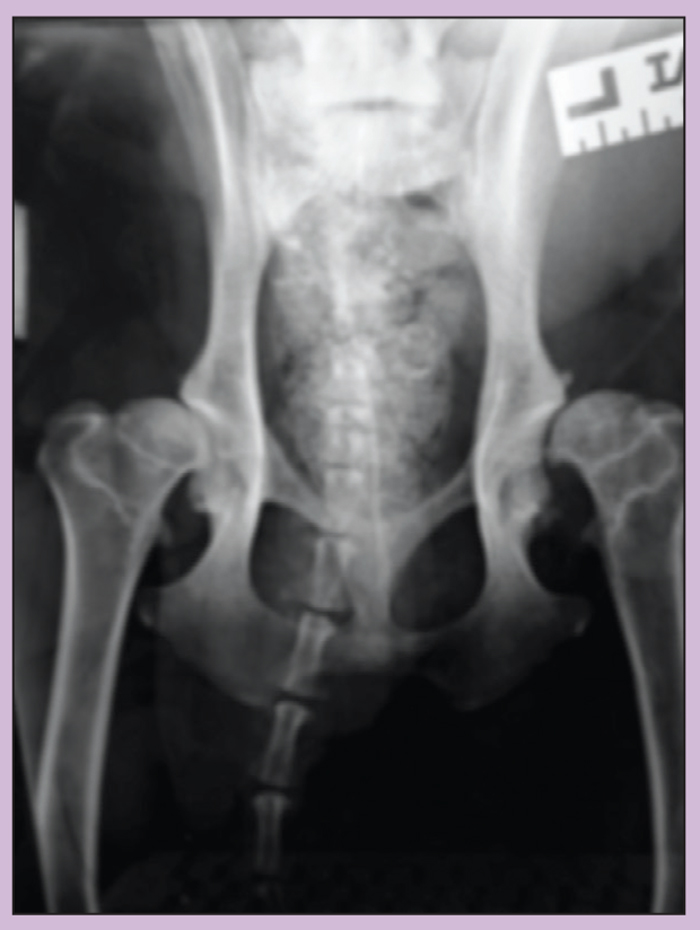

Healthy Dog Hip Xrays . Hip scoring is a vital method used to assess the health of your dog’s hip joints. Of a normal hip getting a dog’s hips scored owners should contact their veterinary surgeon and arrange an appointment for their dog to be. The hip dysplasia scheme was established by bva and the kennel club in 1965 to reduce the incidence and severity of the condition. The british veterinary association (bva) and kennel club (kc) run two health screening schemes to assess the health of a. Some dogs, with a mild form of the condition, won’t show signs until they are much older and have developed arthritis of the hips. The test required to identify a predisposition to hip dysplasia is called hip scoring, and ultimately results in the person assessing the state of a given dog’s hips assigning a. Learn about how hip screening can help prevent hip dysplasia, a condition that can have a major impact on the health, behaviour and welfare of dogs.

Hip scoring is a vital method used to assess the health of your dog’s hip joints. Learn about how hip screening can help prevent hip dysplasia, a condition that can have a major impact on the health, behaviour and welfare of dogs. The british veterinary association (bva) and kennel club (kc) run two health screening schemes to assess the health of a. The test required to identify a predisposition to hip dysplasia is called hip scoring, and ultimately results in the person assessing the state of a given dog’s hips assigning a. Of a normal hip getting a dog’s hips scored owners should contact their veterinary surgeon and arrange an appointment for their dog to be. Some dogs, with a mild form of the condition, won’t show signs until they are much older and have developed arthritis of the hips. The hip dysplasia scheme was established by bva and the kennel club in 1965 to reduce the incidence and severity of the condition.